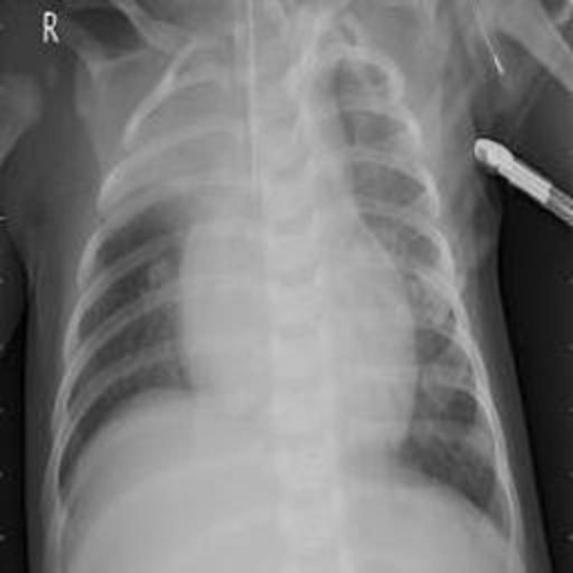

In this project ,we aim to propose a fully-automated method to detect/screen COVID-19 from the patient’s chest X-ray scanned images with out needing a clinical technician.

I've teamed up with AI enthusiasts and got inspired from the several news articles to create a end to end web application using Deep learning.We have collected datasets from Mendeley and Qatar University which were posted on kaggle website.We augumented the images and trained the model to detect the hidden patterns in the images and using "Transfer Learning" approach we have used the model to deploy it on cloud platform and hooked it via flask server.